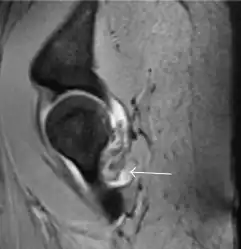

Synovial chondromatosis can be confidently diagnosed by X-ray when calcified cartilaginous chondromas are seen. However, other synovial proliferative processes, such as pigmented villonodular synovitis, require MRI for accurate diagnosis, although noncalcified synovitis can be suspected in radiographs by indirect signs, such as soft tissue swelling and/or erosions in the femoral head, femoral neck, or acetabulum (Figure 7).[1]

Figure 7:

-

Axial CT image of pigmented villonodular synovitis eroding the posterior cortex of the femoral neck.[1] -

Sagittal T2* gradient echo image showing a posterior soft tissue mass with hypointense areas secondary to hemosiderin deposition.[1] -

In synovial proliferative disorders, MRI demonstrates synovial hypertrophy. In the case of PVNS, characteristic foci of low signal intensity related to hemosiderin deposition are better seen on gradient echo T2* images (Figure 7). In the case of synovial osteochondromatosis, the synovial hypertrophy is accompanied by intermediate signal cartilaginous loose bodies and/or low signal calcified loose bodies.[1]